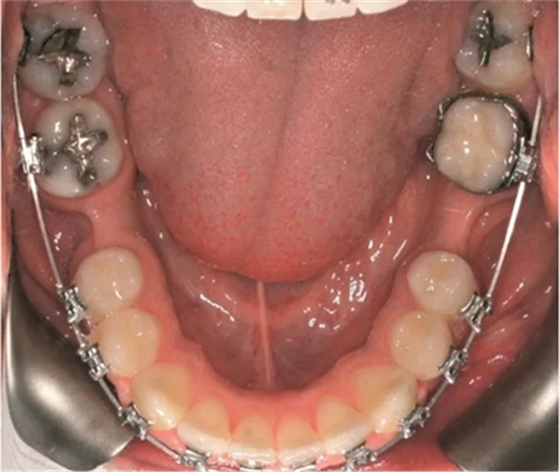

為患者采用了直絲弓自鎖托槽(Damon,Ormco)。最開(kāi)始用0.016×0.025 英寸的不銹鋼弓絲(Damon,Ormco)進(jìn)行矯正和排齊,歷時(shí)7 個(gè)月。在磨牙直立加力之前,下頜第一磨牙位點(diǎn)無(wú)牙區(qū)的近遠(yuǎn)中距離為右側(cè)6.5mm、左側(cè)9mm(圖1)。磨牙遠(yuǎn)移和直立的目標(biāo)是實(shí)現(xiàn)雙側(cè)最終冠修復(fù)體的近遠(yuǎn)中直徑達(dá)到10mm。右側(cè)第一磨牙位點(diǎn)的大小差異比左側(cè)更大,牙槽嵴吸收更多,頰舌徑約4.5mm(圖2)。在詳細(xì)解釋同期牙槽嵴增量和加速磨牙直立程序后,患者選擇右側(cè)位點(diǎn)進(jìn)行種植治療。因此,為了加速該位點(diǎn)的空間建立,圍繞第二磨牙行選擇性去皮質(zhì)術(shù)和同期牙槽嵴增量術(shù)。

術(shù)后即刻,將0.018×0.025英寸的銅鎳鈦(NiTi)弓絲和NiTi 主弓絲套推簧沿著無(wú)牙頜區(qū)域置于雙側(cè),施加半托槽寬度(約1.5mm)的力?;颊咴谧畛醯?個(gè)月中,每2周隨訪(fǎng)一次,之后每月隨訪(fǎng)一次。1個(gè)月后,左側(cè)下頜第一磨牙區(qū)獲得了10mm的近遠(yuǎn)中距離,用被動(dòng)線(xiàn)圈保持。對(duì)側(cè)區(qū)域(右側(cè)第一磨牙)空間通過(guò)主弓絲套推簧和三線(xiàn)圈來(lái)加力(一個(gè)托槽的寬度)。術(shù)后3個(gè)月時(shí),達(dá)到10mm的目標(biāo)(圖2d)。分別在術(shù)前(圖3a)和骨增量5個(gè)月后(圖3b)拍攝右下頜第一磨牙區(qū)域的錐束CT,結(jié)果顯示,成功獲得了5mm的水平骨增量。這樣的增量允許在合適的位置上植入一個(gè)寬直徑的種植體。